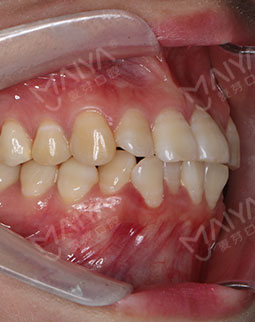

在主任的建议下拔了牙,根据我的牙齿情况,主任做了适合我的矫牙方案。选择了时代天使双膜矫治器,矫治器是透明的,可以自行摘戴,满足了我想矫正又怕丑的要求,让我在别人不知道的情况下,拥有整齐的牙齿,在矫正之前是可以在计算机上模拟显示整个矫治过程中牙齿的变化过程,可以很直观的看到,让我自己感觉心里很放心,经过一个月的等待,终于戴上了牙套,给主任和麦芽点赞!

2017-12-1不让自己留遗憾,我与歪牙要打持久战

经过朋友良心推荐,最终选择了麦芽口腔。在麦芽是张超主任给我检查的牙齿,然后跟着医助拍的片,这期间都有专人负责,张主任很专业的为我定制了方案,当天就取了牙模~